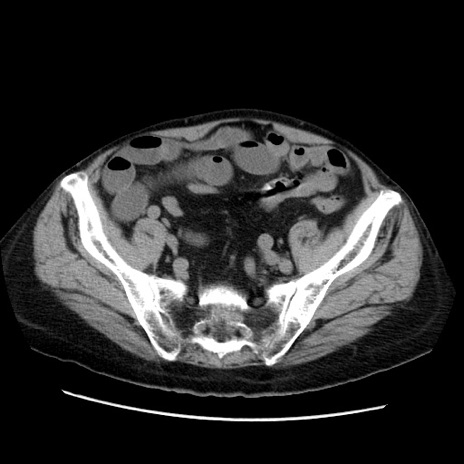

症例21(横断像)

【症例】70歳代男性

【主訴】腹痛

【現病歴】肝硬変・肝細胞癌にてかかりつけの方。約9時間前に食後より腹痛出現。症状が徐々に増悪し、嘔吐出現したため来院。

【既往歴】肝硬変、肝細胞癌(RFA、TACE後)

【身体所見】意識清明、表情苦悶様、BT 36℃、BP 129/78mmHg、P 88bpm、SpO2 97%(RA)、右上腹部から心窩部にかけて圧痛あり、反跳痛なし、筋性防御あり。

【データ】WBC 5800、CRP 0.16